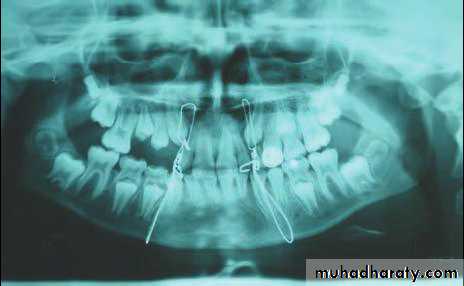

When an isolated mandibular fracture is suspected, the routine radiographic assessment may consist of a panoramic radiograph and one additional postero-anterior view of the mandible, usually an open-mouth Towne’s radiograph.Additional periapical or occlusal radiographs are often helpful in viewing specific areas of concern in more detail, especially when dental or alveolar fractures are suspected.